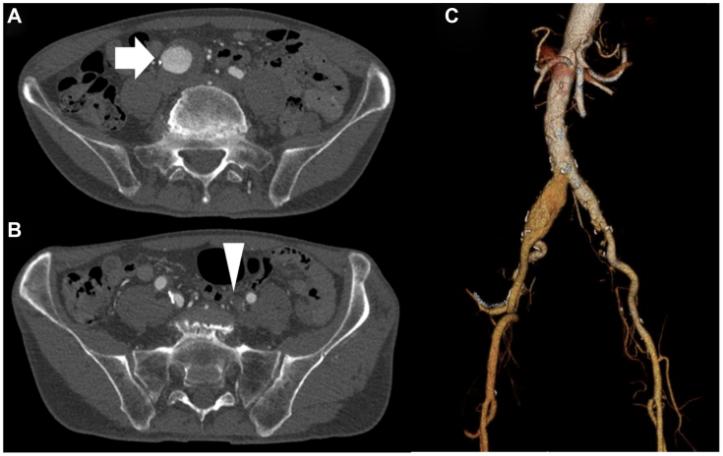

1例74岁幕上肿瘤男性患者因右侧髂总动脉动脉瘤就诊于我院。既往有高血压病史。增强 CT 显示:右侧髂总动脉动脉瘤(直径 32mm),左侧髂内动脉闭塞(图1);主髂动脉长度146mm,右侧髂总动脉长度52mm;腹主动脉末端直径20mm,未发现腹主动脉瘤(Abdominal Aortic Aneurysm,AAA)。患者拟行幕上肿瘤放化疗,需术后快速恢复。由于左侧髂内动脉闭塞,保留右侧髂内动脉灌注至关重要。因此,我们计划为该患者实施IBE联合EVAR术。但主髂动脉及右侧髂总动脉长度不满足Excluder与IBE常规联用的条件,故计划在左侧腹主动脉末端上方15mm处释放Excluder髂动脉延长器,以缩短最低肾动脉与腹主动脉末端的距离,并选择AFX作为近端支架。

图1术前 CT:A.白色箭头示右侧髂总动脉动脉瘤;B.白色箭头示左侧髂内动脉闭塞;C.三维CT示最低肾动脉与腹主动脉末端距离缩短